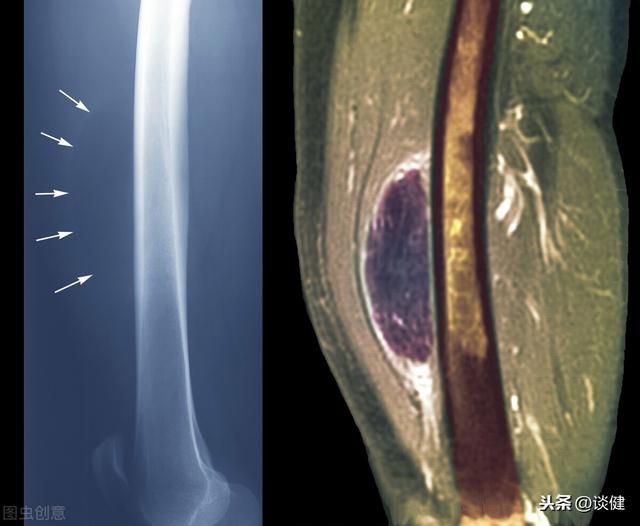

脂肪腫は、正常な脂肪組織から形成される腫瘍様の腫瘤で、通常は近くの筋肉に付着していない薄い被膜に囲まれている。脂肪腫は身体の正常な脂肪組織から形成されるため脂肪が体内のどこにでも存在する場合、脂肪腫が成長する可能性がある。とはいえ、ほとんどの脂肪腫は、そのような場所を好む。肩、背中、首、女性乳房、ヒップなどの皮下脂肪組織に発生し、脂肪腫は一般的にゆっくりとした無害な成長.まれに、筋肉や胃や腸などの内臓に脂肪腫ができることがある。

脂肪腫のある人の90~95%は腫瘍が1つしかなく、大きさも通常2~3cmと小さい。しかし、脂肪腫が多発する人は少数派で、時には10cm以上に成長することもあります。

通常、脂肪腫は症状を引き起こさないが、大きくなりすぎると、脂肪腫の近くの皮下組織を圧迫することがある。神経、血管その結果、痛みやしびれを感じることもあります。また、脂肪腫が消化管の近くにでき、比較的大きい場合は、腹痛や腸閉塞の発症など、さまざまな症状を引き起こすこともあります。

脂肪腫は皮下で発生することが最も多く、少数の患者はまた体の深い部分で発生し、ほとんどの患者は特別な不快感を持っていない、皮下で発生した場合、塊で見つけることができ、柔らかい質感、良好な可動性、脂肪腫瘍末梢神経や血管の圧縮のために少数の患者は、痛みを伴う症状が表示されることがあります。